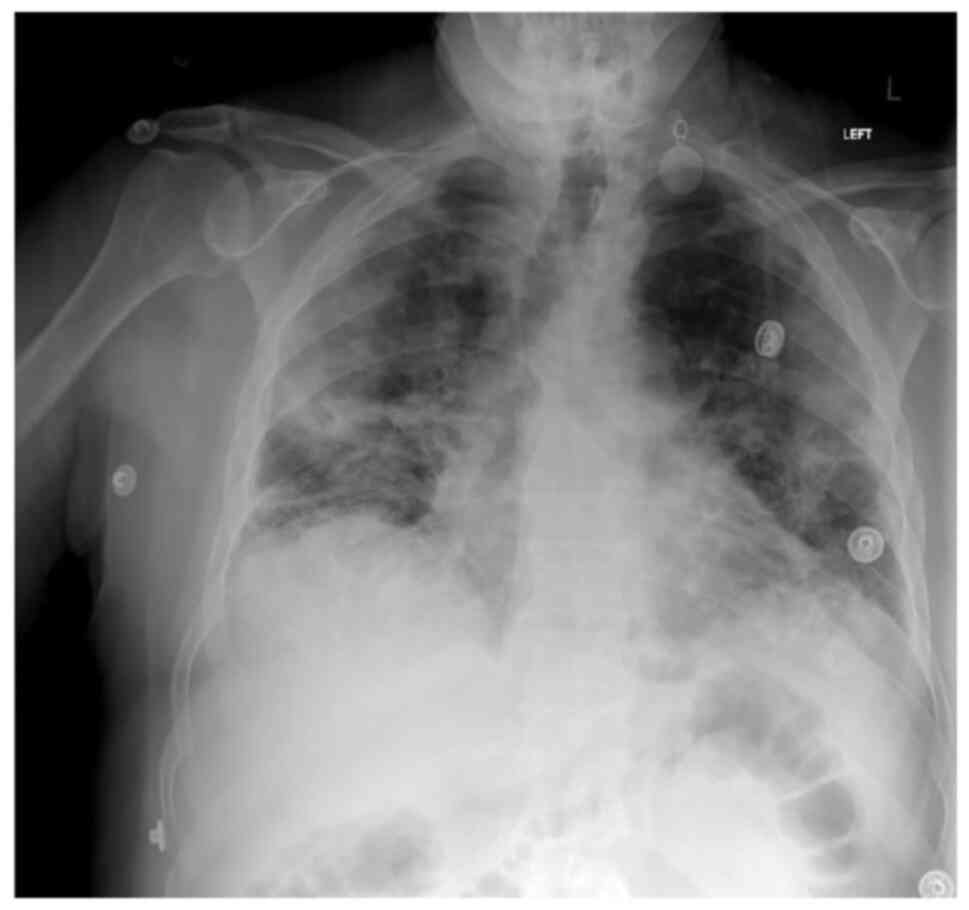

Upon admission, his body temperature was 37.4˚C, his blood pressure was 120/70 mmHg, his heart rate was 94 beats per minute, his respiratory rate was 32 breaths per minute, and his oxygen saturation (SpO2) was 92% in room air. A chest examination revealed crackles on auscultation in all lung fields. Arterial blood gases analysis revealed a partial pressure of oxygen (pO2) of 56 mmHg, partial pressure of carbon dioxide (pCO2) 31 mmHg, pH 7.51, HCO3 24.7 mmol/l on room air. A chest X-ray revealed diffuse infiltrates in all lung fields (Fig. 1). The laboratory findings included an increased white blood cell (WBC) count (11.22 k/µl; reference range, 4.5-11 k/µl) with neutrophilia (87.4%; reference range, 40-74%) and lymphopenia (6.63%; reference range, 19-48%), elevated C-reactive protein (CRP) levels (151.77 mg/l; reference range 0-5 mg/l), elevated lactate dehydrogenase (LDH) levels (331 U/l; reference range, 135-225 U/l) and elevated ferritin levels (1,200 ng/ml; reference range, 30-400 ng/ml).

Figure 1

Chest X-ray illustrating diffuse infiltrates in all lung fields in the patient in case 1 upon admission.